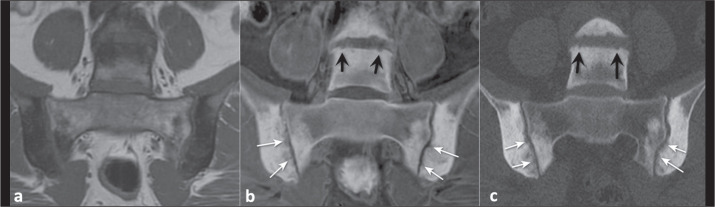

Increasing tissue contrast for bone assessment on magnetic resonance imaging has been the aim of several recent studies, and various techniques have been proposed for that purpose, including ultrashort echo time sequences, zero echo time sequences, and gradient echo sequences in various acquisition forms. In this article, we discuss the fast field echo resembling a computed tomography using restricted echo-spacing (FRACTURE) sequence, which we have started to use routinely in our practice. The FRACTURE sequences are based on the acquisition of gradient echo sequences with different echo times and specific postprocessing. Gradient echo sequences are widely available on magnetic resonance imaging scanners, which is an advantage for the use of a FRACTURE sequence. However, being more susceptible to metal artifacts, a FRACTURE sequence is of limited utility in patients with metallic implants or medical devices. The aim of this article is to illustrate the use of FRACTURE sequences in various contexts, including osteoarticular infection, inflammatory arthropathy, bone tumors, fractures, and crystal deposition diseases.